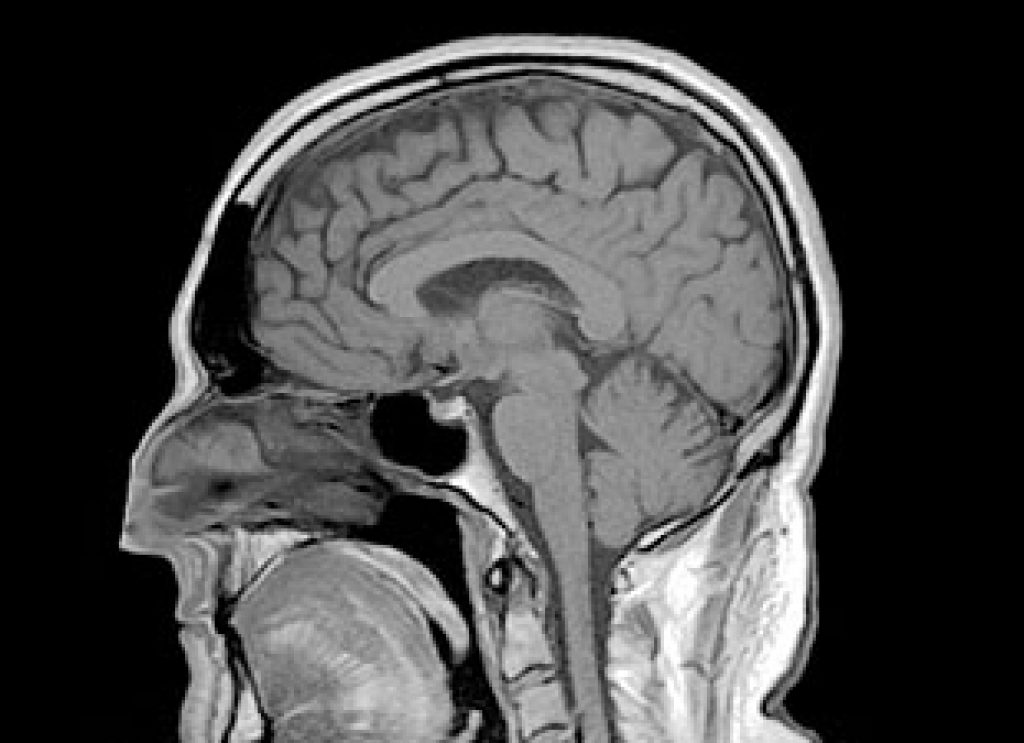

AsianScientist (Apr. 3, 2013) – Plaque, long considered to be the hallmark of Alzheimer’s disease, is one of the last events to occur in the Alzheimer’s brain, says a new study.

The Investigators found that significant nerve cell loss and a range of brain pathologies, including inflammation, began at the same time as subtle memory problems appeared, early in the disease process. Plaques occurred much later, well after significant memory loss.

“Our study supports the increasingly common view that treatment should start much earlier in the disease process. It also suggests that brain inflammation and cell loss may be an earlier indicator of disease pathology than plaque and an alternative target for treatment.”